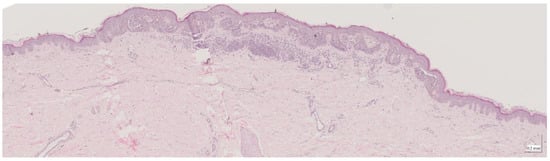

| Intradermal nevus (IN) Case 1 | Localization: right forefoot (sole) |

![]() | ![]() |

| Intradermal nevus (IN) Case 2 | Localization: left dorsal |